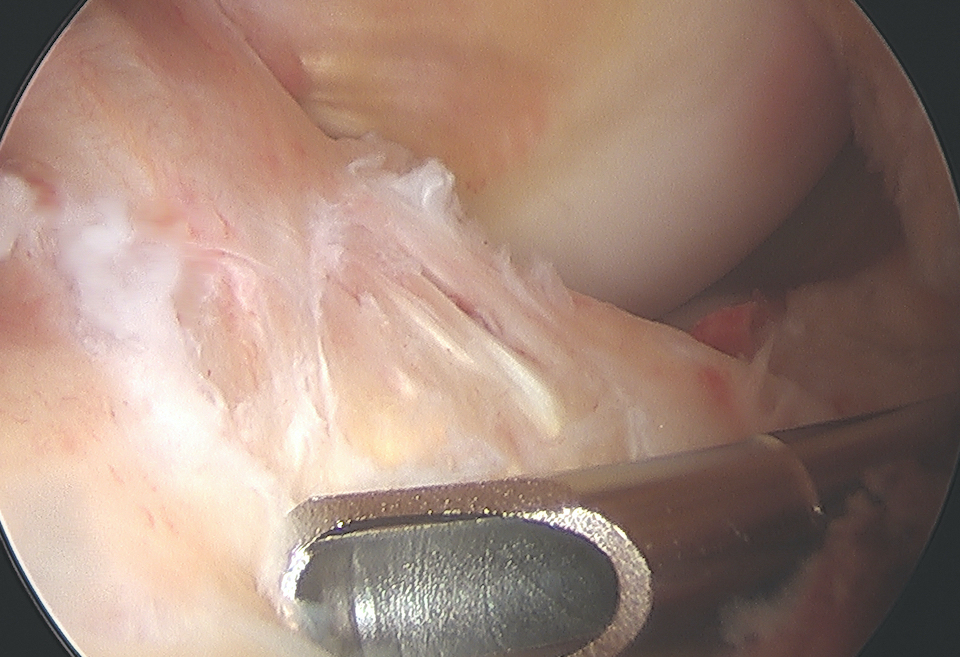

Arthroscopic suture fixation

Fragment flipped and insertion debrided Avulsion fragment reduction Passage of two loop sutures with scorpion

Clean haematoma, ensure can reduce fragment with probe

Reduce fragment and hold with ACL tibial guide

1. Passing sutures anterior to the bony fragment rather than through may help anatomical reduction